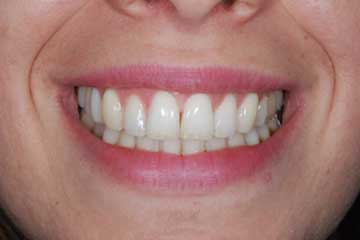

Faccette estetiche in ceramica

Riabilitazione gnatologica, ortodontica ed estetica

Durata del trattamento: un anno